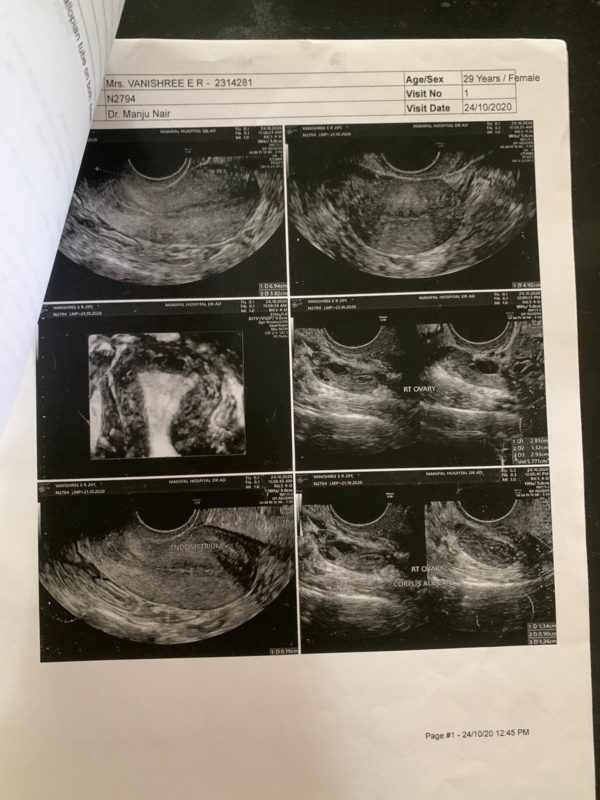

The images of the USG scan shows

1. Pre-

Pre – Right ovary showed a cyst with internal echoes suggestive of corpus albicans. Right side hydrosalphinx with chronic inflammation of the walls. Bilateral fallopian tube with inflamed walls. Left ovary appeared normal with a follicle